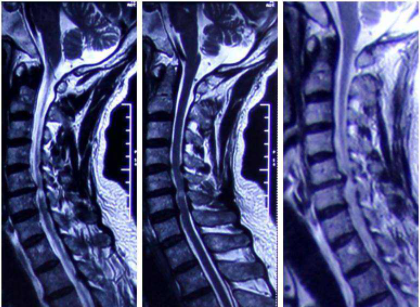

就在2020年10月16号,我在公司的厕所里倒下了。还好当时有好心人帮我一把,把我搀扶到工位。事态已经严重到如此地步了,我决定去区里的医院求救下,当天就来到人民医院急诊科,因为那时我已经迷迷糊糊了。来到医院后,医生给我先开了个头颅CT检查,并给我诊断为椎动脉型颈椎病。

我问医生我这到底是个什么情况,他给我的官方答复是:我是由于颈椎形成骨刺或者半脱位而压迫了椎动脉,出现椎基底动脉供血不足的表现,从而导致出现眩晕、头疼和视觉障碍这些症状。在治疗完后医生还给我开了防风通圣颗粒(3克/20袋,一天两次一次一包)+华医郎医用冷敷贴(一天一贴,一次八个小时)。